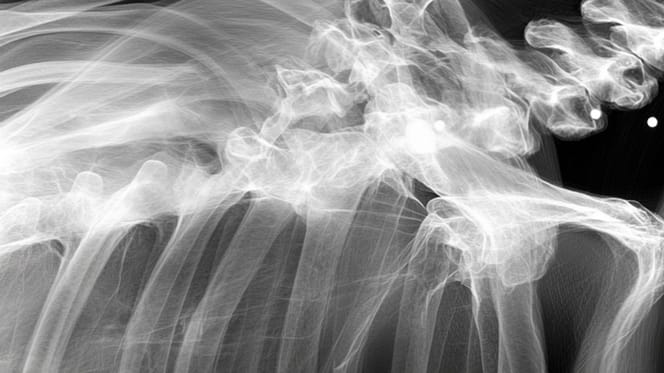

Jednak z czasem jej opiekunka zauważyła, że jej ukochana suczka zaczyna mieć problemy z poruszaniem się. Martwiąc się o nią, zabrała ją do weterynarza na badania i prześwietlenie. Wtedy wydarzyło się coś, co dosłownie ścięło wszystkich z nóg.

W gabinecie u weterynarza, po obejrzeniu zdjeć RTG zapadła cisza. Po chwili lekarz wyjaśnił, że suczka prawdopodobnie miała za sobą bardzo trudną, pełną przemocy przeszłość.

Zdjęcie rentgenowskie wykazało, że wszystko wskazuje na to, że była wykorzystywana w pseudohodowli. Ale to nie wszystko. Suczka, która cierpiała również na zapalenie stawów i dysplazję stawu biodrowego, skrywała jeszcze jeden sekret.

Weterynarz wkrótce odkrył również, że ciało suczki było podziurawione kulami z broni palnej. Jedna z nich przeszła bardzo blisko kręgosłupa. Na szczęście żadna z kul nie miała poważniejszych konsekwencji dla życia suczki, która dziś ma wszystko, o czym zawsze marzyła, jak donoszą nasi koledzy z Newsweeka.